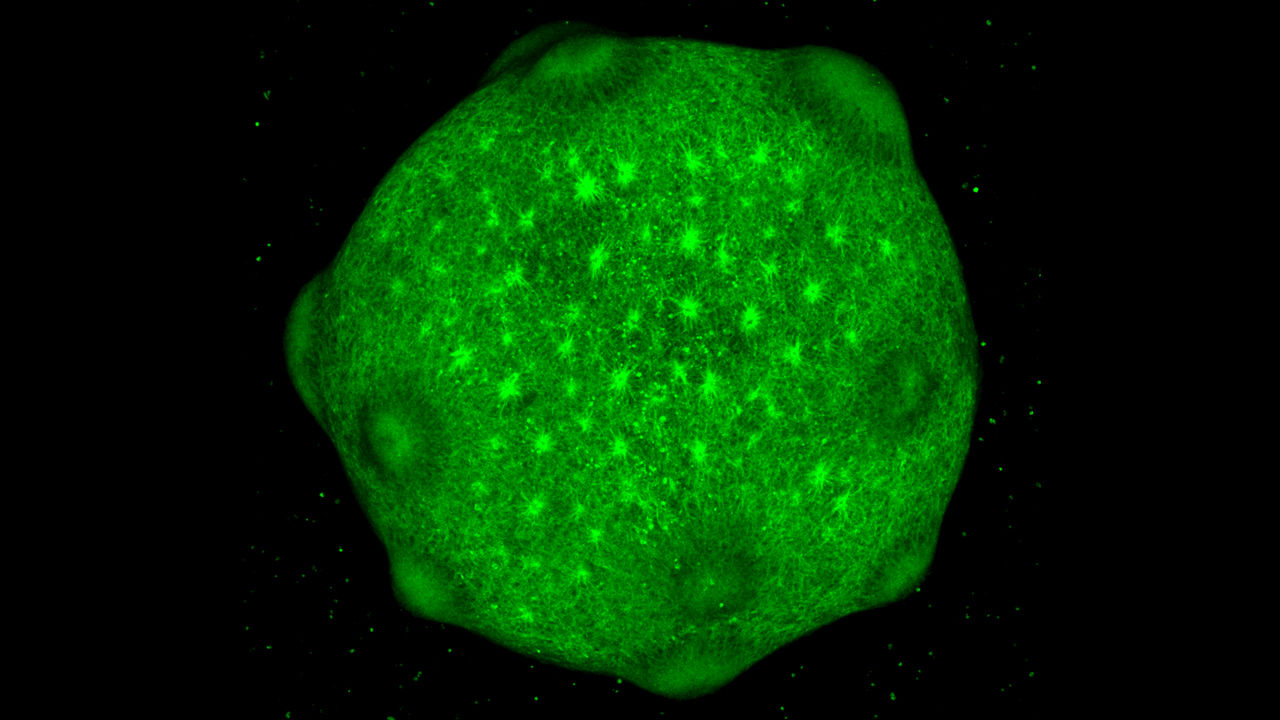

과학자들은 난치병 치료를 위해 수년 전부터 인간의 줄기세포에서 유래된 오가노이드(organoid·미니 장기) 뇌를 배양하여 인체의 내부 시스템을 모방하고 연구해왔다. 하지만 이렇게 배양된 세포들은 일반적으로 수명이 길지 않을뿐더러 진짜 인간의 뇌처럼 성장할 수 있는지에 대해 의문이 많았다.

그런데 실험실에서 배양된 미니 뇌도 충분한 시간이 주어지면 인간 뇌 발달의 전체 단계를 모방하는 방식으로 성장하고 성숙할 수 있다는 사실이 밝혀졌다.

미국 로스앤젤레스 캘리포니아주립대(UCLA)의 다니엘 게쉬윈드(Daniel Geschwind) 박사와 스탠퍼드대학의 세르기우 파스카(Sergiu Pasca) 박사는 실험용 접시에서 최대 20개월 동안 배양된 오가노이드 뇌에 대해 광범위한 유전자 분석을 실시했다.

그 결과 연구진은 그 같은 미니 뇌들이 태아, 출생 후, 유아기 등 인간의 발달 단계에 맞추어 정렬되는 내부 시계를 따른다는 사실을 발견했다. 이 연구 결과는 뇌신경 과학 분야 저명 국제 학술지인 ‘네이처 뉴로사이언스(Nature Neuroscience)’ 2월 22일 자에 게재됐다.

연구진은 유도만능 줄기세포가 뇌의 특정 부위 세포를 생성하도록 특정 성분의 성장 촉진 영양소에 노출시켰다. 그 후 적절한 조건과 시간이 주어지면 세포들은 인간 두뇌 발달의 여러 면을 충실히 복제하는 3D 구조를 만들기 위해 스스로 조직화된다.

연구진은 오가노이드 뇌의 유전자 발현을 다른 연령대의 인간 뇌세포에서 나온 RNA의 데이터베이스와 비교했다. 그 결과 배양한 지 약 9개월이 되었을 때 오가노이드 뇌의 유전자 발현이 출생 직후 인간의 뇌에서 나온 세포의 발현과 매우 밀접하게 닮아간다는 사실을 발견했다.

이번 연구의 저자 중 한 명인 UCLA 게쉬윈드 연구실의 애런 고든 박사는 “오가노이드 뇌는 배양한 지 280일 정도 될 때 성숙기에 도달했으며, 그 이후에는 신경전달물질 신호로 알려진 생리학적 변화를 포함하여 유아 뇌의 측면을 모델링 하기 시작했다”고 밝혔다.

또한 오가노이드의 세포 덩어리는 혈관, 면역, 감각적 입력 등을 포함한 주요 특징들이 부족하다. 그러나 실험용 접시라는 부자연스러운 조건에서도 오가노이드가 어떻게 발달을 진행할지를 알고 있다는 사실은 놀랄 만한 일이라고 파스카 박사는 주장했다.